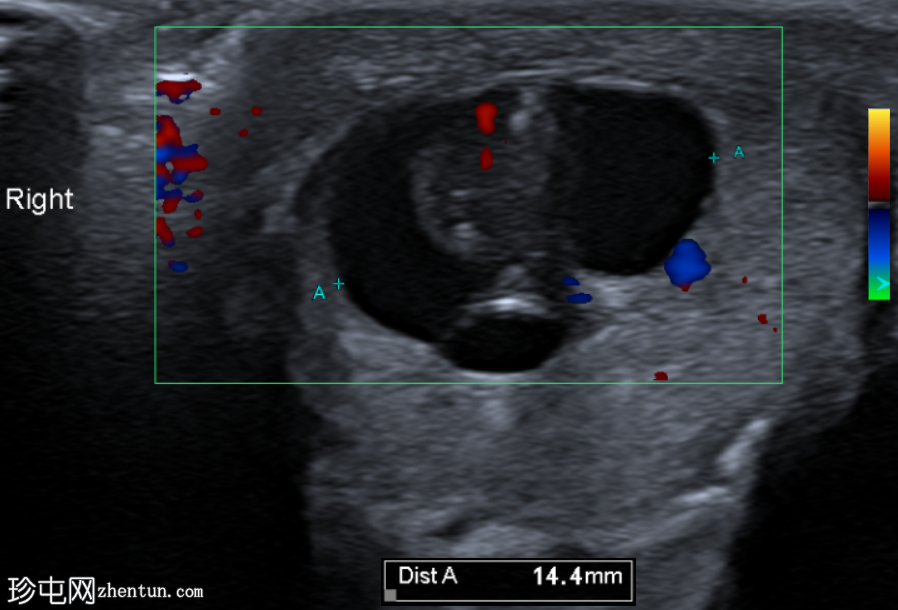

右侧睾丸内可见一异质性肿块,大小约10 x 14 x 15 mm,包含实性和囊性成分。肿块内可见多发小钙化灶。彩色多普勒超声检查显示肿块内血流信号较少。